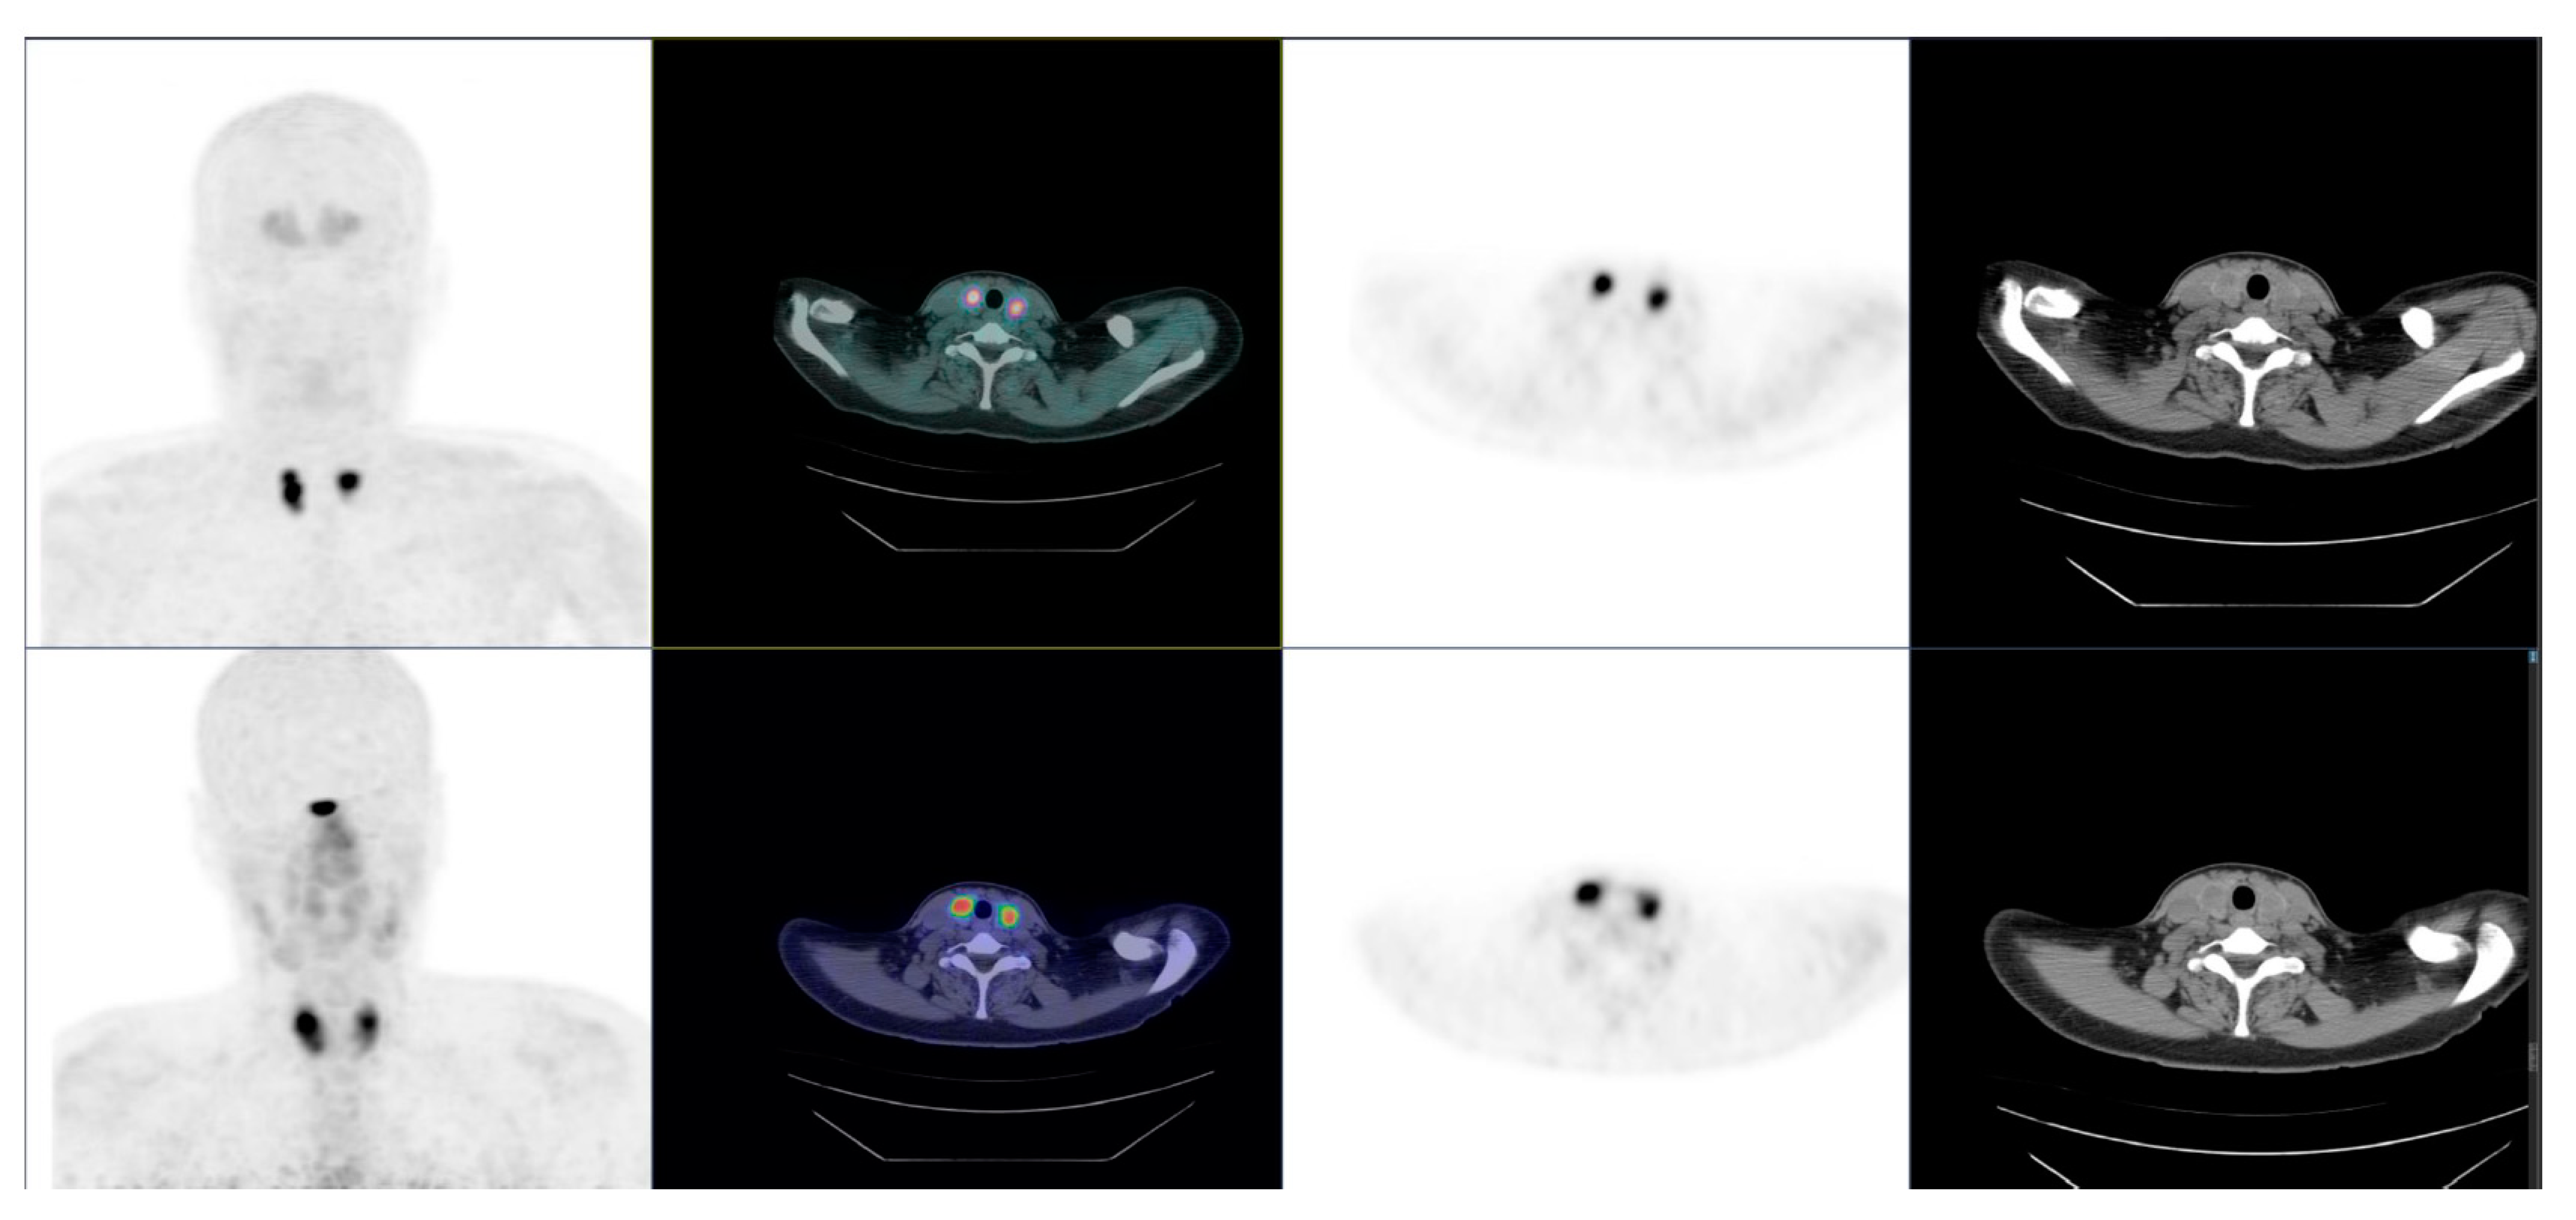

- Rasul, S.; Hartenbach, S.; Rebhan, K.; Göllner, A.; Karanikas, G.; Mayerhoefer, M.; Mazal, P.; Hacker, M.; Hartenbach, M. [18F]DOPA PET/ceCT in diagnosis and staging of primary medullary thyroid carcinoma prior to surgery. Eur. J. Nucl. Med. Mol. Imaging 2018, 45, 2159–2169. [Google Scholar] [CrossRef] [Green Version]

- Asa, S.; Sonmezoglu, K.; Uslu-Besli, L.; Sahin, O.E.; Karayel, E.; Pehlivanoglu, H.; Sager, S.; Kabasakal, L.; Ocak, M.; Sayman, H.B. Evaluation of F-18 DOPA PET/CT in the detection of recurrent or metastatic medullary thyroid carcinoma: Comparison with GA-68 DOTA-TATE PET/CT. Ann. Nucl. Med. 2021, 35, 900–915. [Google Scholar] [CrossRef] [PubMed]